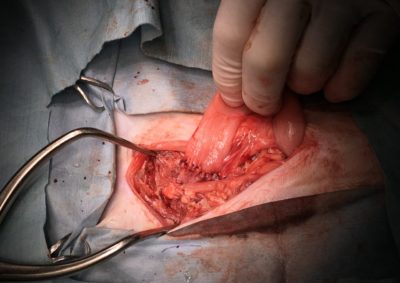

腫瘍外科 注意 ボタンをクリックした先に、治療中および手術中の画像が説明で使用されている場合がございます。 そのような画像に弱い方は閲覧なさらないようお願いいたします。 腫瘍外科 フレンチブルドッグ胃腺癌 胃部分切除 軟部組織外科腫瘍外科救急・集… 肝臓腫瘤破裂による腹腔内出血 腫瘍外科腫瘍内科 猫の直腸切除吻合 直腸リンパ腫 腫瘍外科 犬の肺腺癌の1例 腫瘍外科放射線治療 犬の軟部組織肉腫に対する腫瘍辺縁切除及び術後放射線療法 腫瘍外科 犬の肝細胞癌 軟部組織外科腫瘍外科 ジャックラッセルテリアの胃腫瘍 腫瘍外科 吻側下顎骨切除術〜メラノーマ〜 腫瘍外科 猫の上顎腫瘍切除 腫瘍外科 犬の脾臓腫瘤摘出 軟部組織外科腫瘍外科 大腸腺癌 軟部組織外科腫瘍外科 肺葉切除術 <1234567> 症例カテゴリー 放射線治療整形外科軟部組織外科脳神経外科内科腫瘍外科救急・集中治療リハビリテーション科腫瘍内科内視鏡科脳神経科呼吸器外科中医・漢方猫の腎移植循環器科